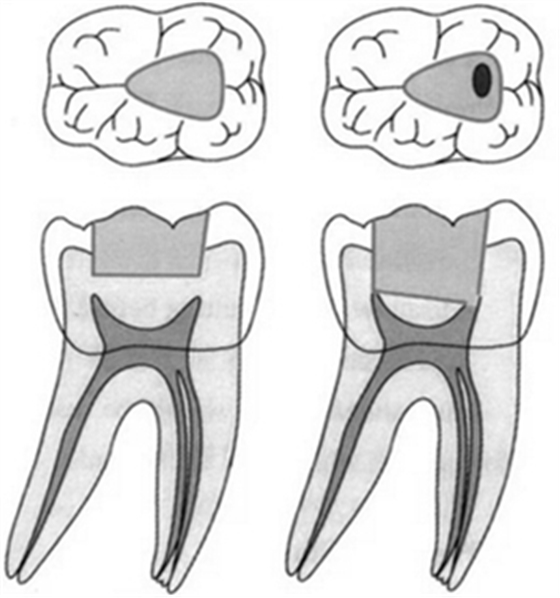

Ⅰ型 從根管口至根尖為1個根管(圖a)。

Ⅱ型 2個獨立的根管自根管口發(fā)出,在根尖上方合并成1個根管(圖b)。

Ⅲ型 2個獨立的根管分別開口于2個分開的根尖孔(圖c)。

Ⅳ型 1個根管自根管口發(fā)出,在根尖上方分成2個獨立的根管并開口于2個根尖孔(圖d)。

其他人還有一些補充,其實很少見,吳有農(nóng)和岳保利的分類很全面,但過于復(fù)雜,臨床應(yīng)用不太方便,到是做一些研究的時候很好用。